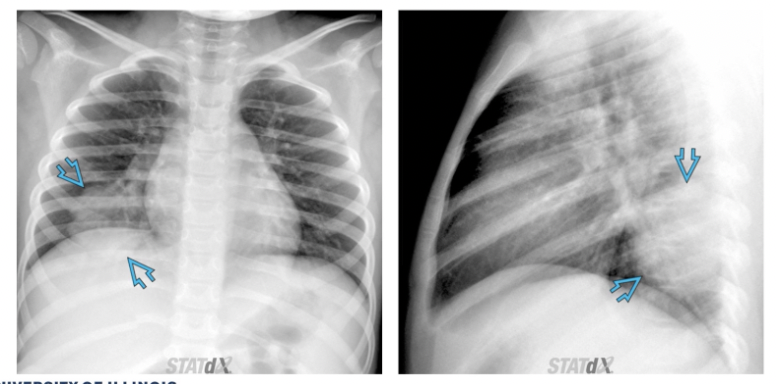

What CXR radiographic findings are typical for round pneumonia

• Spherically shaped consolidations in the posterior lower lobes, mostly seen in patients younger than 8